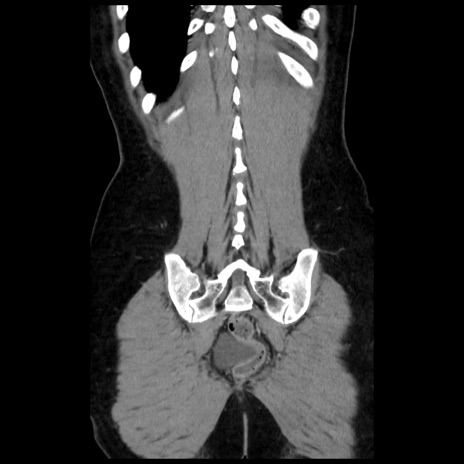

症例10(冠状断像)

【症例】 50歳代女性

【主訴】 腹痛

【現病歴】前日生レバーを食べた。今朝に排便あり。 昼前に突然発症の腹痛を生じ、当院救急外来を受診した。

【既往歴】 子宮筋腫にてで子宮全摘後

【身体所見】 意識清明、腹部:平坦、軟、下腹部やや左を中心に圧痛・反跳痛あり、筋性防御あり

【データ】WBC 7800、CRP 0.07

矢状断像